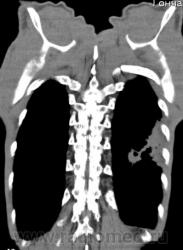

КТ - ОГК.  Ваше мнение коллеги?

На фоне консолидации полость без содержимого. Может быть всё что угодно, что сопровождается деструкцией. Нужны ещё томограммы в лёгочном окне.

Изображения выставлены все. Ваше мнение уважаемые коллеги?

Туберкулёз.

Туберкулёз?